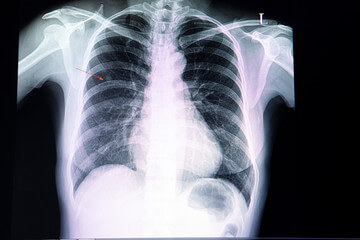

폐결절은 폐에 형성되는 작은 덩어리 또는 종양을 의미합니다. 이러한 결절은 폐의 X선이나 기타 영상 검사를 통해 발견될 수 있으며 다양한 원인에 의해 발생할 수 있습니다. 폐결절은 종종 미립자, 감염, 염증, 혹은 기타 조직의 비정상적인 성장으로 인해 형성될 수 있습니다.

흉부 X선 검사

폐결절은 보통 흉부 X선으로 처음 발견될 수 있습니다. X선은 폐결절의 크기와 일반적인 특징을 파악하는 데 도움이 될 수 있습니다. 그러나 X선은 폐결절의 세부적인 특성을 파악하기에는 제한적일 수 있습니다.